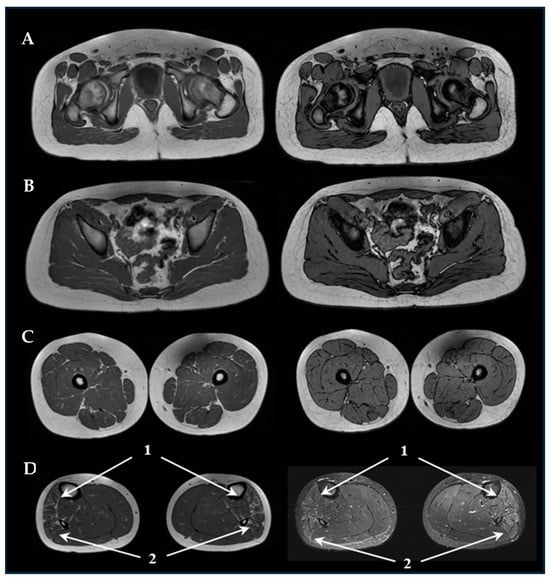

3.2. Neurophysiology and Neuroimaging